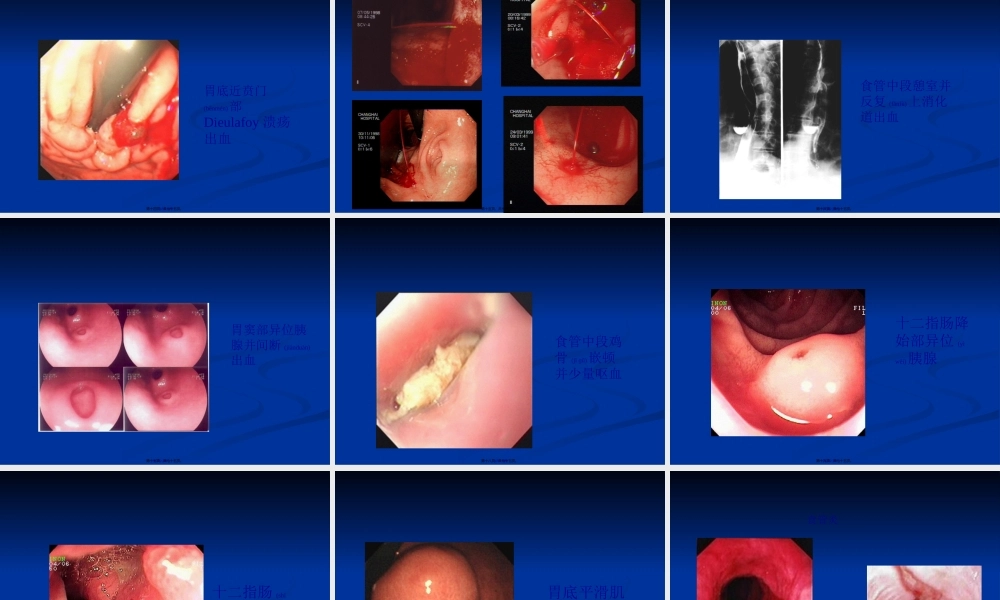

急性非静脉曲张性上消化道出血急性非静脉曲张性上消化道出血(chū(chūxiě)xiě)内镜下治疗技术内镜下治疗技术苏州大学附一院消化(xiāohuà)内科李岭第一页,共七十五页。ANVUGIB系指屈氏韧带以上的消化道的非静脉曲张性疾患(jíhuàn)引起的出血,包括胰管或胆管的出血和胃空肠吻合术吻合口附近疾患(jíhuàn)引起的出血,年发病率为50-150/10万。病死率6-10%。(中国)发病年龄高峰:30~90岁男性∶女性=2∶1死亡率:4.7%第二页,共七十五页。急性非静脉曲张性上消化道出血(acutenonvaricealuppergastrointestinalbleeding,ANVUGIB)是急诊科常见的问题(wèntí),随着内镜技术的普及和发展,ANVUGIB的诊治取得显著进步。第三页,共七十五页。1.出现呕血、黑便症状及周围循环衰竭体征,急性上消出血诊断基本可成立。2.内镜检查无胃底静脉曲张并在上消化道发现有出血病灶,ANVUGIB可确立。3.下列可误诊:某些口、鼻、咽部或呼吸道出血被吞入,服用某些药物和食物引起黑便。对可疑可作胃液、呕吐物或粪便隐血(yǐnxuè)试验。4.部分出血量大,肠蠕动过快也可出现血便。少数仅有周围循环衰竭征象,而无显性出血,不应漏诊。第四页,共七十五页。上消化道出血(chūxiě)病因第五页,共七十五页。(bìngyīn)消化性溃疡消化性溃疡急性胃粘膜病变急性胃粘膜病变门脉高压性胃病门脉高压性胃病(wèibìnɡ)(wèibìnɡ)消化道肿瘤消化道肿瘤胆道出血胆道出血Mallory-WeissMallory-Weiss综合征综合征((食管贲门黏膜撕裂综合食管贲门黏膜撕裂综合征征))DieulafoyDieulafoy病病((杜氏病杜氏病))残窦综合征(是指残窦综合征(是指BillrochⅡBillrochⅡ式手术时,胃窦式手术时,胃窦切除不全,残留胃窦所致的切除不全,残留胃窦所致的吻合口溃疡症候群。残留胃吻合口溃疡症候群。残留胃窦复发性溃疡的发病率为窦复发性溃疡的发病率为4040%)%)异位异位(yìwèi)(yìwèi)胰腺胰腺Zollinger-EllisonZollinger-Ellison综合征综合征第六页,共七十五页。(chūxiě)消化性溃疡(kuìyáng)第七页,共七十五页。消化性溃疡(kuìyáng)第八页,共七十五页。消化性溃疡(kuìyáng)伴出血第九页,共七十五页。(chūxiě)急性(jíxìng)胃粘膜病变第十页,共七十五页。(chūxiě)胃癌第十一页,共七十五页。食道癌第十二页,共七十五页。(chūxiě)十二指肠降部平滑肌肉瘤(ròuliú),溃烂伴出血第十三页,共七十五页。(chūxiě)胃...

1、当您付费下载文档后,您只拥有了使用权限,并不意味着购买了版权,文档只能用于自身使用,不得用于其他商业用途(如 [转卖]进行直接盈利或[编辑后售卖]进行间接盈利)。

2、本站所有内容均由合作方或网友上传,本站不对文档的完整性、权威性及其观点立场正确性做任何保证或承诺!文档内容仅供研究参考,付费前请自行鉴别。

3、如文档内容存在违规,或者侵犯商业秘密、侵犯著作权等,请点击“违规举报”。

碎片内容

蜗牛文库的最新文档

二年级数学下册其中检测卷二年级数学下册其中检测卷附答案#期中测试卷.pdf

10.00金币

0下载